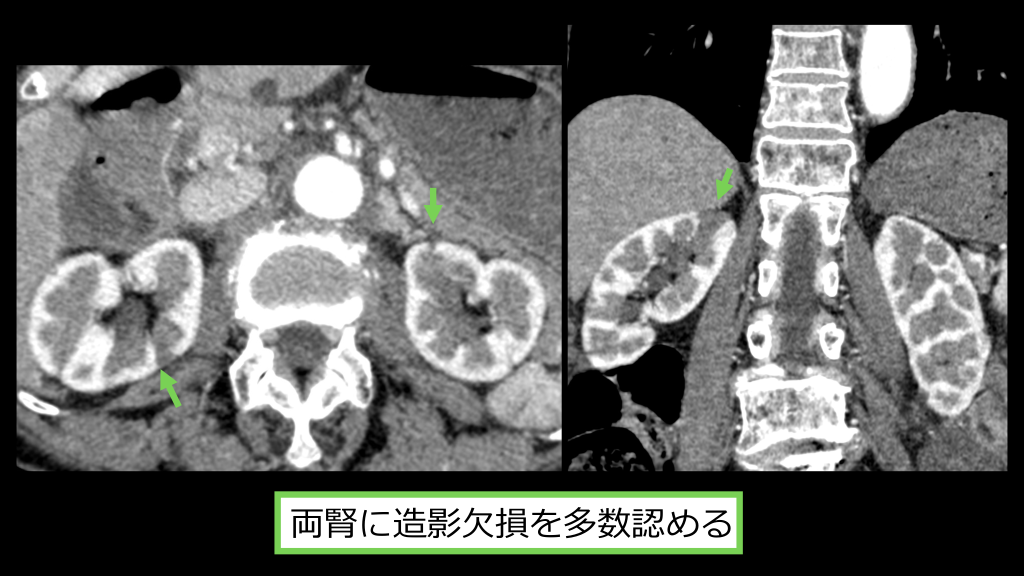

両腎に造影⽋損を多数認める